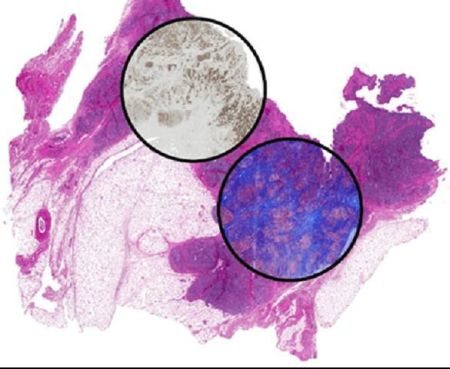

Researchers at the University of Illinois at Urbana-Champaign have developed a new approach to histology based on using infrared (IR) microspectroscopy. Instead of using stains, the spectra measure the chemical constitution of cells and tissues directly.

By using computational techniques, the researchers—led by Rohit Bhargava, a professor in the university's Bioimaging Science and Technology Group—were able to relate spectral properties to known staining patterns of tissue. The outcome is that that molecular stains can be reproduced without staining the tissue, but by using the intrinsic molecular contrast of the tissue and computation. That means any sample can be stained for desired stains without material cost, time, or effort while leaving precious tissue pristine for downstream analyses.

Another use of the approach can be in the analysis of small amounts of samples—for example, from a thin needle biopsy. In cases where materials are limited or there may be a need to closely correlate multiple expressed molecules, it may not be possible to obtain multiple samples from the same biopsy for multiple stains. The method developed in this study could be a solution, allowing the user to simply "dial-in" a required stain. The study is timely, as it builds on the emergence of chemical imaging and maturation of computation from the sciences/engineering side and the drive to greater molecular content from the biomedical/clinical side. The development of this approach promises to have immediate and long-term impact in changing pathology to a multiplexed molecular science—in both research and clinical practice.